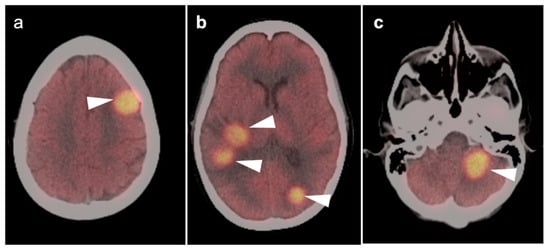

3.5. Brain Metastases

3.6. Response to Therapy

3.7. Meningioma